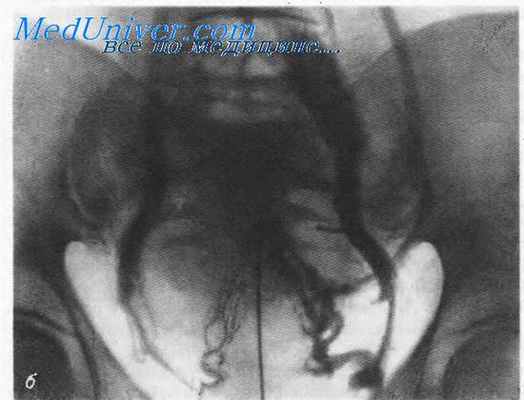

Чрезматочная флебография.

Чрезматочная флебография

Чрезматочная флебография (metrophlebographia intramuralis). Для ее производства необходимо иметь 20-граммовый шприц, специальный маточный проводник и иглу с ограничителем. Исследование проводится на рентгеновском столе.

При чрезматочной флебографии после обнажения влагалища зеркалами передняя и задняя губы шейки матки захватываются пулевыми щипцами и зондируется полость матки. В соответствии с направлением ее оси вводится металлический (Guiljem) или фторопластовый (А. Е. Маркман) проводник. Последний более удобен, так как не обладает рентгеноконтрастностью, а также позволяет придать ему любой изгиб вследствие эластичности. Он не опасен также и в отношении возможности перфорации матки.

При чрезматочной флебографии проводник продвигается до дна матки, и через него затем вводится игла, имеющая на конце, который присоединяется к шприцу, специальный пелот (ограничитель), препятствующий выдвижению острого конца иглы за пределы проводника более чем на 4 мм. Игла вкалывается в толщу мышцы матки в области дна (по возможности его середины) и вводится затем 20 мл водорастворимого контрастного вещества (диодон, кардиотраст и т. д.). Снимки производятся через 10 и 20 секунд.